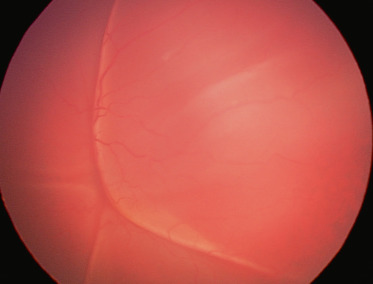

- l’échographie, souvent couplée au Doppler, est un examen clé dans les pathologies rétiniennes de l’enfant (fig. 19-1). Elle permet en cas de trouble des milieux de diagnostiquer : le décollement et ses caractéristiques de topographie, de mobilité, de vascularisation ; les déchirures ; l’état du vitré ; les lésions associées, etc. Son rôle pour éliminer un rétinoblastome, toujours redouté dans les pathologies du segment postérieur de l’enfant, est essentiel ;

Fig. 19-1 Échographie : le Doppler permet d’objectiver les vaisseaux de la rétine décollée.

(Remerciements au Dr O. Bergès.)